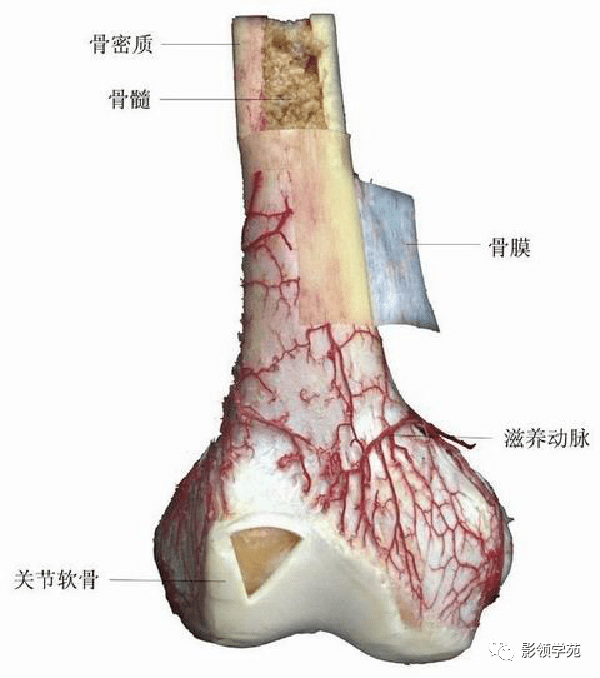

骨骼系统

骨骼系统